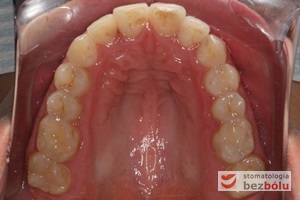

Pacjentka lat 22 zgłosiła się do naszej placówki celem podjęcia leczenia ortodontycznego. Głównym oczekiwaniem pacjentki była poprawa estetyki uśmiechu oraz brak ekstrakcji zębów na drodze do jej uzyskania. Ze względu na liczne stłoczenia zębów w górnym i dolnym łuku, dość duży materiał zębowy w porównaniu z bazą kostną, a także zgryz przewieszony boczny prawostronny po dokładnej analizie cefalometrycznej oraz analizie modeli diagnostycznych zastosowano leczenie bezekstrakcyjne z wykorzystaniem strippingu jako alternatywy dla usuwania zębów, mającego na celu uzyskanie miejsca w łuku na uszeregowanie zębów. Po fazie aktywnego leczenia trwającego 18 miesięcy zastosowano leczenie retencyjne w postaci szyny retencyjnej w łuku górnym oraz retainera stałego w łuku zębowym dolnym klejonego od kła do kła.